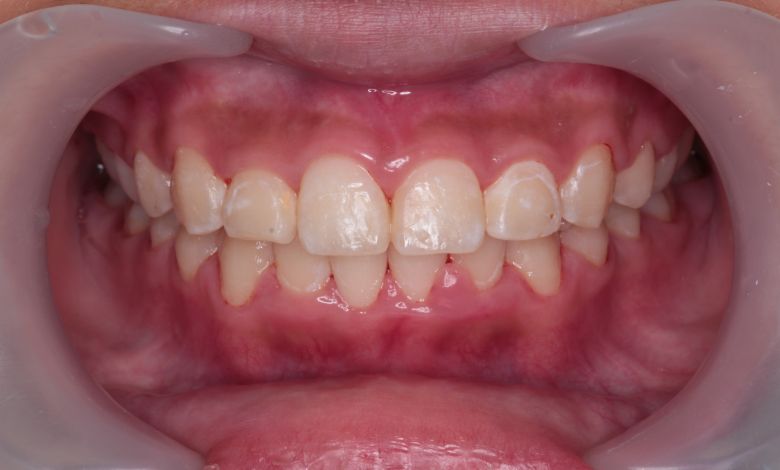

正常な咬合関係が確立され、前歯の自然なアーチと歯軸も整い、歯列全体が滑らかなカーブを描く美しい歯並びに

上下の歯がしっかりと噛み合う、美しい咬合(こうごう)が得られた

精密検査の結果、当院では抜歯を行わず、歯列弓の拡大によってスペースを確保し、非抜歯での矯正治療を選択しました。歯列の叢生(ガタガタ)は解消され、機能的かつ審美的に優れた咬合が得られました。

上下の前歯の重なりが解消され、歯軸の傾きも整いました。咬合関係も安定しています

上下の前歯の重なりや段差は完全に解消され、咬合関係も安定してる。自然なスマイルラインが形成され、口元の印象も大きく改善された